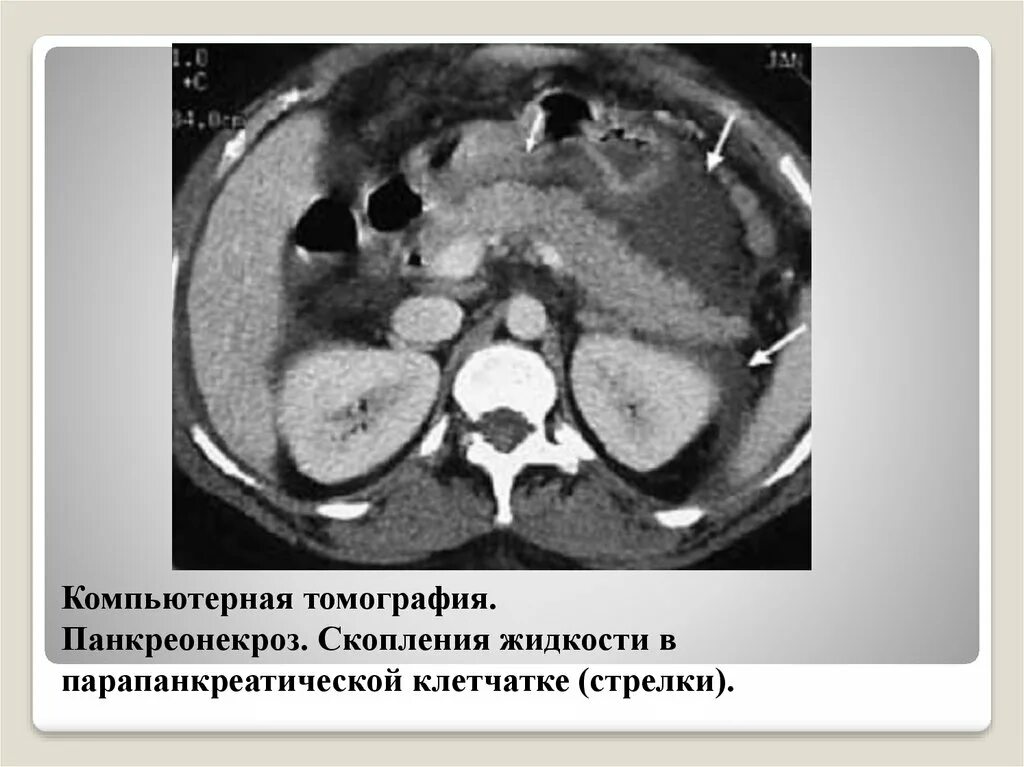

Инфильтрация паранефральной клетчатки на кт. параколитическая клетчатка кт. парапанкреатическая клетчатка инфильтрирована. перипанкреатический инфильтрат.Кт при остром панкреатите. парапанкреатическая клетчатка. кт диагностика панкреатита. острый отечный панкреатит кт.Парапанкреатическая клетчатка. поддиафрагмальное пространство. внебрюшинное поддиафрагмальное пространство. парапанкреатическая клетчатка инфильтрирована.Парапанкреатическая клетчатка что это значитКлетчатка анатомия. понятие о клетчатке в анатомии. основы клинической анатомии. клетчатка понятие.Парапанкреатическая клетчатка что это значитПарапанкреатическая клетчатка. парапанкреатическая клетчатка инфильтрирована. парапанкреатическая инфильтрация. парапанкреатическая клетчатка дифференцирована.Парапанкреатическая клетчатка что это значитПарапанкреатическая клетчатка что это значитХронический панкреатит на кт. парапанкреатическая клетчатка на кт. кт поджелудочной железы. поджелудочная железа на рентгенограмме.Парапанкреатическая клетчатка что это значитПарапанкреатическая клетчатка что это значитПарапанкреатический инфильтрат. парапанкреатическая клетчатка дифференцирована.Парапанкреатическая клетчатка что это значитПарапанкреатическая клетчатка что это значитПарапанкреатическая клетчатка поджелудочной железы. отек парапанкреатической клетчатки. парапанкреатическая инфильтрация. острый деструктивный панкреатит кт.Парапанкреатическая клетчатка что это значитПарапанкреатическая клетчатка что это значитПарапанкреатическая клетчатка что это значитПарапанкреатическая клетчатка что это значитПарапанкреатическая клетчатка что это значитПарапанкреатический инфильтрат. перипанкреатический инфильтрат. парапанкреатическая псевдокиста на кт.Парапанкреатическая клетчатка что это значитПарапанкреатическая клетчатка что это значитПарапанкреатическая клетчатка что это значитПарапанкреатическая клетчатка что это значитПарапанкреатическая клетчатка что это значитПарапанкреатическая клетчатка что это значитПарапанкреатическая клетчатка что это значитПарапанкреатическая клетчатка что это значитПарапанкреатическая клетчатка что это значитПарапанкреатическая клетчатка поджелудочной железы. перипанкреатический инфильтрат. осложнения острого панкреатита презентация. перипанкреатическая клетчатка.Парапанкреатическая клетчатка что это значитКисты и свищи поджелудочной железы. инфильтрация парапанкреатической клетчатки. истинные кисты поджелудочной железы классификация. парапанкреатическая клетчатка поджелудочной железы.Парапанкреатическая клетчатка что это значитПарапанкреатическая клетчатка что это значитПарапанкреатическая клетчатка что это значитПарапанкреатическая клетчатка что это значитПарапанкреатическая клетчатка что это значитПарапанкреатическая клетчатка что это значит